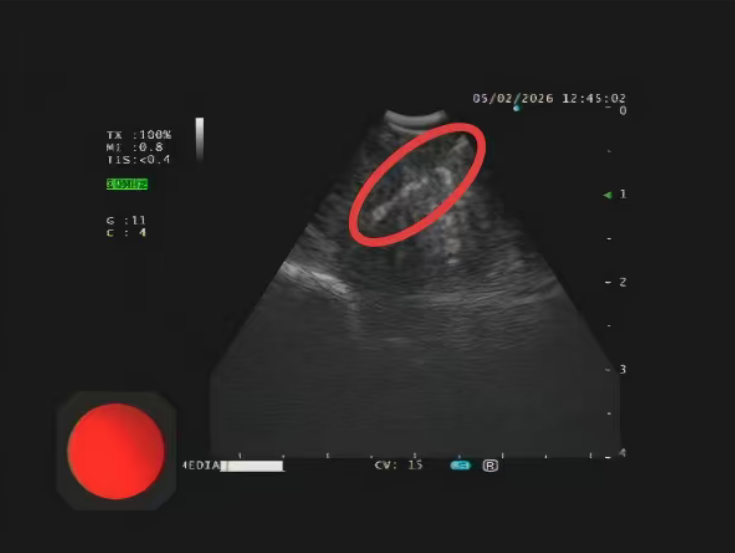

面对这一棘手问题,我院迅速启动多学科会诊机制。耳鼻咽喉头颈外科与呼吸与危重症医学科专家深入讨论后,提出突破性方案——借助超声支气管镜(EBUS)经鼻腔,对鼻咽后壁深部病灶实施实时影像引导下针吸活检。

术中依托超声支气管镜实时成像系统,动态显示病灶位置及周围血管结构,实现穿刺路径可视化。

在精准导航下,穿刺针准确进入MRI所示可疑结节区域,同时有效避开重要血管和神经结构,大幅提升操作安全性与取材成功率。

在多学科团队密切配合下,手术顺利完成并成功获取有效组织标本。最终病理结果明确为鼻咽癌转移灶阳性。